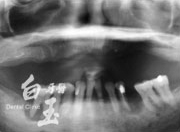

植入植體